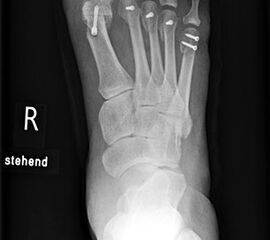

Die primäre Therapie von belastungsabhängigen Beschwerden im Vorfußbereich ist konservativ. Im Rahmen der Diagnostik werden Röntgenbilder des ganzen Fußes im Stehen angefertigt, um die statischen und funktionellen Verhältnisse des Vor- und Rückfußes zu beurteilen.

• Klinische Untersuchung, Anamnese, Bildgebung mit Röntgen des Fußes unter Belastung in mindestens 2 Ebenen.

Die Fäden werden nach der 2. postoperativen Woche gezogen. Der Verbandsschuh wird für 4-6 Wochen getragen, anschließend erfolgt eine Röntgenkontrolle (Abb.16). Das Führen eines Kraftfahrzeuges mit diesem Schuh ist nicht gestattet. Eine Ausnahmekombination stellt die Operation des linken Fußes und Automatik-Fahrzeug dar.